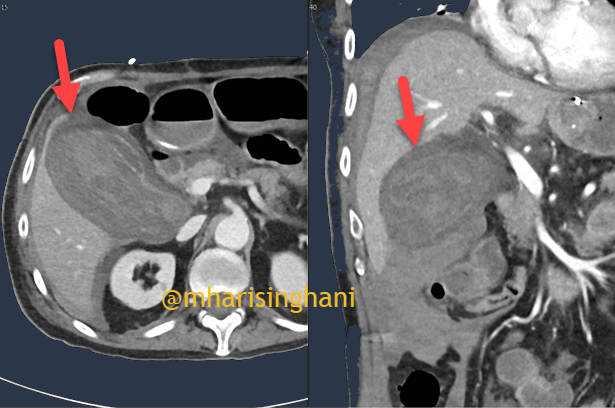

Patient on anticoagulation with spontaneous hemorrhagic cholecystitis